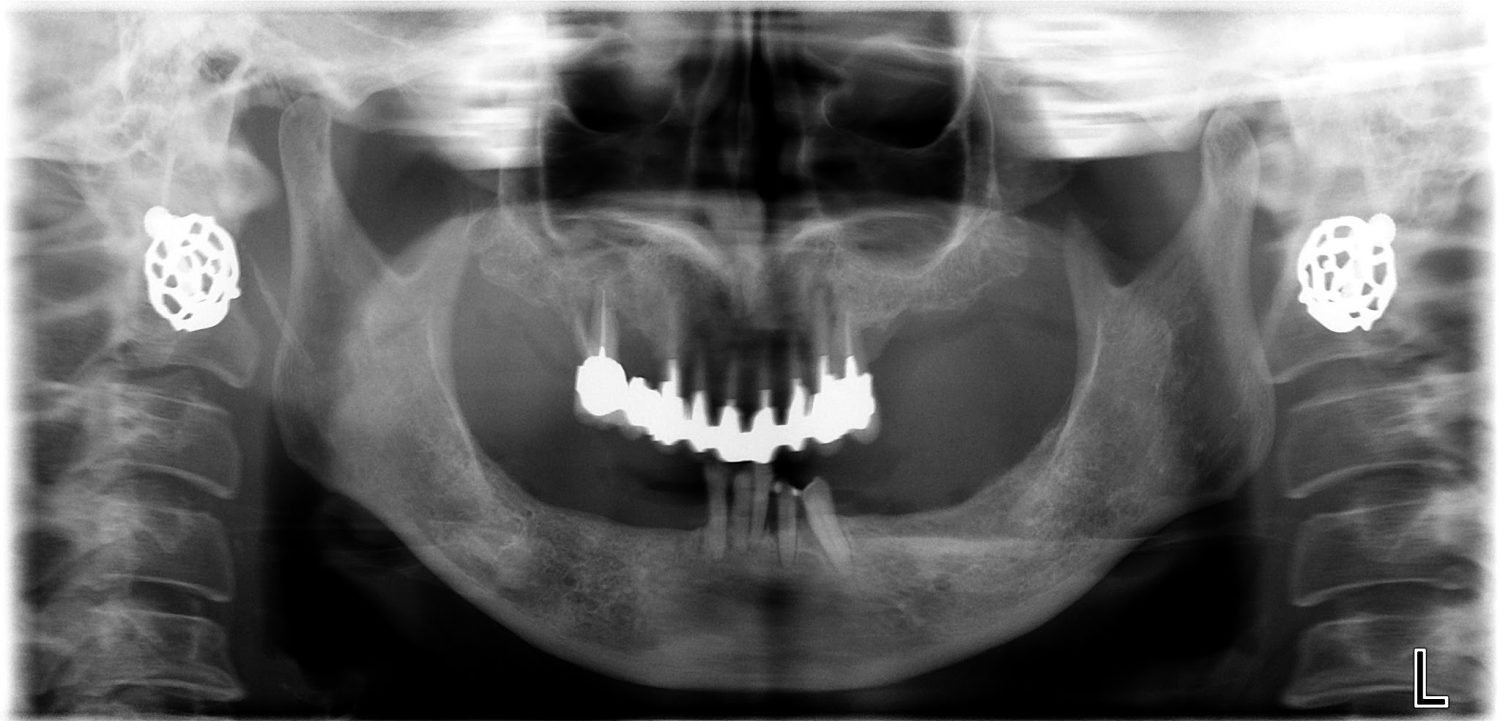

インプラント治療の症例紹介③

Before

After

主訴

むし歯の治療

治療内容

保存不可能な歯の抜歯

下顎にインプラント埋入し咬合再構成

治療費

2,688,400円(税込)

治療期間

14か月

治療回数

21回

想定されたリスク

※上部構造の形態が複雑になるため清掃が難しくなる。インプラント周囲炎の恐れがありました。

多数歯う蝕および多数歯欠損による咬合崩壊、保存不可能な歯の抜歯により上下無歯顎に。下顎に6本インプラント埋入する事で咬合再構成を行った。